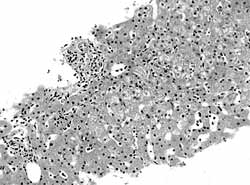

肺表面瀰漫性出血切面可見水腫和陳舊的出血。鏡檢見肺泡內出血,肺泡腔內常有吞噬含鐵血黃素的吞噬細胞局灶性肺泡纖維組織增殖。免疫螢光檢查顯示肺泡間隔和肺毛細血管基膜有免疫球蛋白和C3呈線狀沉積,腎臟病理改變似急進性腎小球腎炎此外,早期腎小球毛細血管呈局灶和節段性壞死,後期腎小球周圍有淋巴細胞浸潤為一特點。

肺出血-腎炎綜合徵4、腎活檢 除了常規光鏡檢查外,通常需要進行直接免疫螢光染色。免疫介導的肺泡出血綜合徵同時有腎受累時,則腎病理為壞死性腎小球腎炎,組織學改變的程度不同,從輕的系膜增厚至嚴重的新月體性腎小球腎炎,腎動脈血管炎則很少。各種疾病的免疫螢光染色有不同表現,抗基底膜抗體(ABMA)病沿腎小球基底膜有線樣沉積,膠原血管病及特發性免疫複合物介導的腎小球腎炎呈顆粒狀沉積,而PIGN的免疫螢光檢測為陰性,聯合血清學ANCA、ABMA、ANA等檢測能夠提高對診斷、治療和預後的判斷意義。